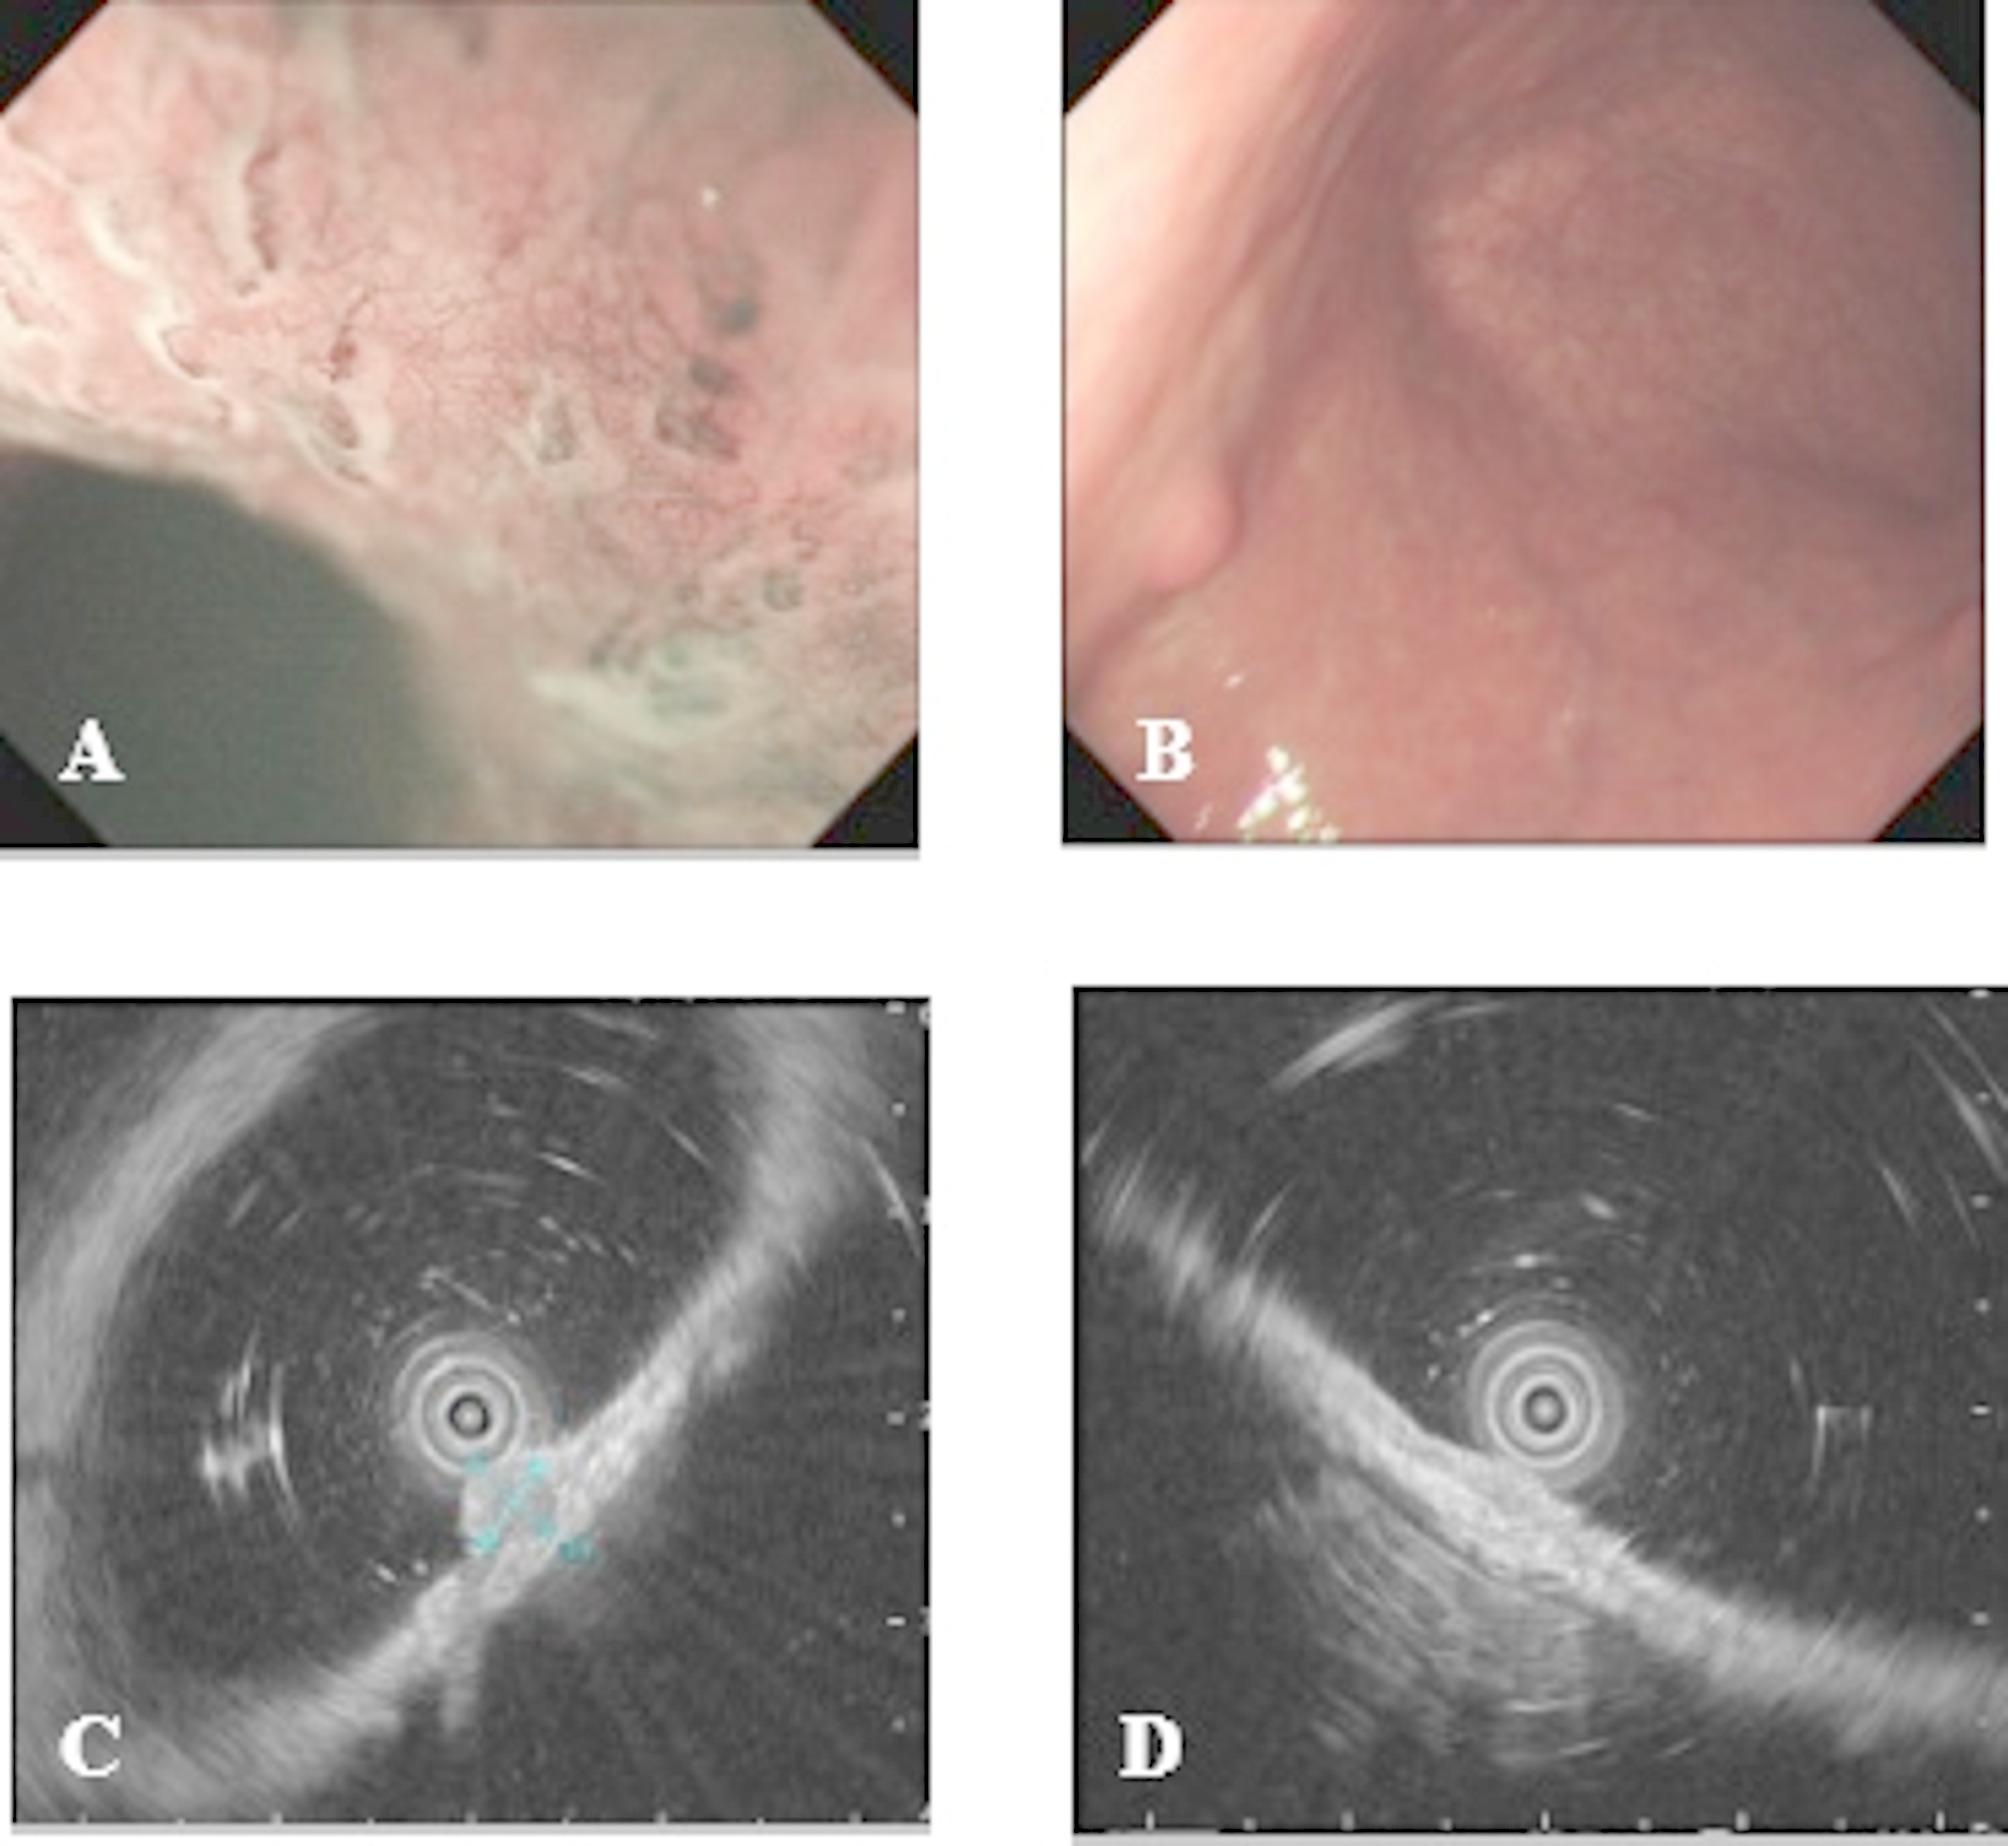

Concomitant gastric cancer and neuroendocrine tumours in the stomach: a rare case series of 3 patients and a literature review.

{"title":"Concomitant gastric cancer and neuroendocrine tumours in the stomach: a rare case series of 3 patients and a literature review.","authors":"Luyu Liu, Weilu Ding, Zhenzhen Wang, Gongning Wang, Limian Er","doi":"10.1186/s13000-025-01704-4","DOIUrl":null,"url":null,"abstract":"","PeriodicalId":11237,"journal":{"name":"Diagnostic Pathology","volume":"20 1","pages":"100"},"PeriodicalIF":2.3000,"publicationDate":"2025-08-29","publicationTypes":"Journal Article","fieldsOfStudy":null,"isOpenAccess":false,"openAccessPdf":"https://www.ncbi.nlm.nih.gov/pmc/articles/PMC12395632/pdf/","citationCount":"0","resultStr":null,"platform":"Semanticscholar","paperid":null,"PeriodicalName":"Diagnostic Pathology","FirstCategoryId":"3","ListUrlMain":"https://doi.org/10.1186/s13000-025-01704-4","RegionNum":3,"RegionCategory":"医学","ArticlePicture":[],"TitleCN":null,"AbstractTextCN":null,"PMCID":null,"EPubDate":"","PubModel":"","JCR":"Q2","JCRName":"PATHOLOGY","Score":null,"Total":0}